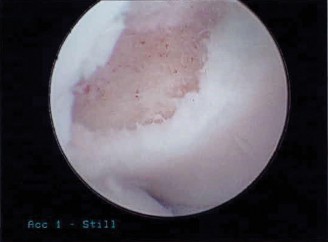

Figure 1: Pre-operative MRI displaying a significant osteochondritis dissecans lesion of the capitellum with associated edema and possible fragment instability. Such imaging is critical for surgical planning.

Magnetic Resonance Imaging (MRI):

The preferred advanced imaging modality. MRI provides detailed information on cartilage integrity, subchondral bone edema, the presence of a fluid signal at the lesion-host interface (indicative of instability), and identification of loose bodies. T1, T2, and proton density sequences with fat suppression are essential.

Lesion staging systems (e.g., DIPA classification, modified Iwase classification, or specific MRI-based criteria) categorize OCD lesions based on articular surface integrity, fragment stability, and subchondral changes. Crucially, MRI findings of instability (e.g., high T2 signal fluid rim beneath the fragment, cartilage breach, loose body) often differentiate between lesions amenable to conservative management and those requiring surgical intervention.